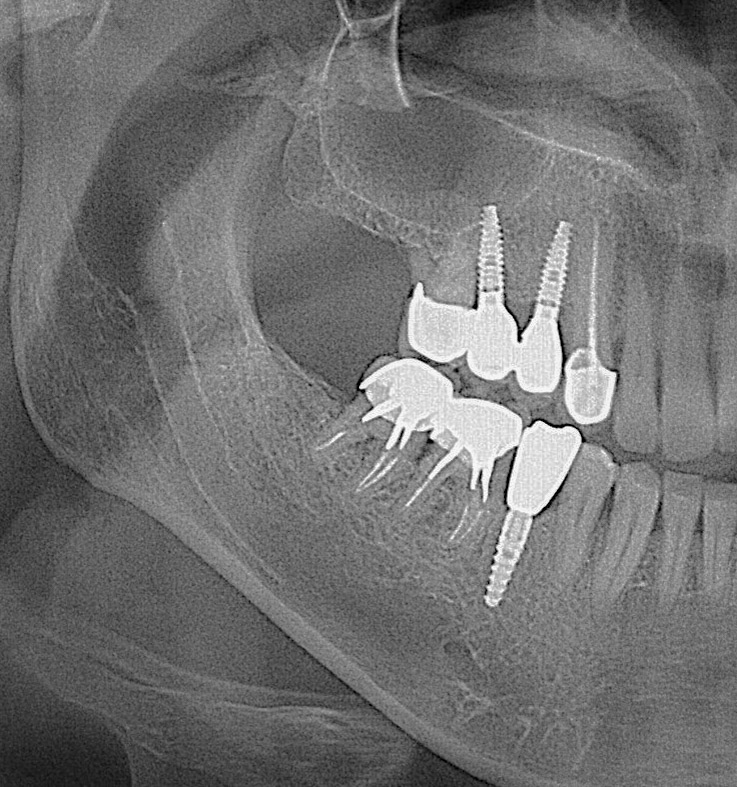

Виконує операцію на віртуальній моделі з оцінкою будови та товщини кістки, а також можливості встановлення імплантату. Імпланти підбираються індивідуально для кожного пацієнта, залежно від клінічної ситуації та завдання.

Абсолютно безболісно встановлюється імплантат у правильну позицію завдяки сучасним апаратам сканування 3 Д діагностики з подальшим виготовленням шаблону для імплангтації.

Суть даної методики полягає в тому, що одночасно можливе видалення зубів з постановкою імплантатів плюс, якщо в цьому є необхідність, відразу ж проводиться кісткова пластика і пластика м’яких тканин навколо імплантатів і в найкоротші терміни виготовляються тимчасові зуби.